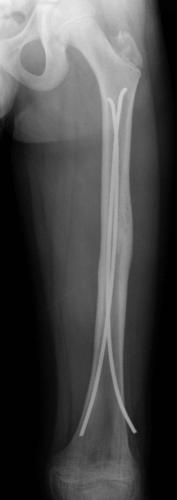

Fracture du fémur – ECMES 9 février 2024 par Damien Fracture diaphysaire du fémur G Fracture diaphysaire du fémur G : radiographie de FaceOn note un chevauchement et un déplacement en varus Fracture diaphysaire du fémur G Fracture diaphysaire du fémur G après Embrochage Centro-médullaire Elestique Stable. Radiographie post-opératoire de Face Fracture diaphysaire du fémur G Fracture diaphysaire du fémur G après Embrochage Centro-médullaire Elestique Stable. Radiographie de Face à 6 mois